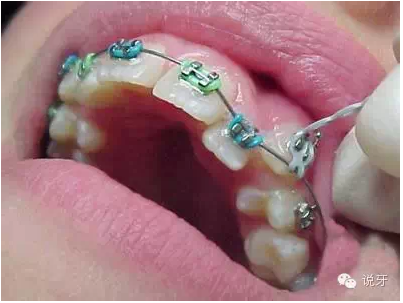

6、分牙

有的分牙是在拔牙時候同時進(jìn)行的,有的則是在拔牙后進(jìn)行。方法是用分牙圈套在上下左右的大牙之間,一般需要分1個禮拜左右。目的是為了使牙齒移出一點(diǎn)空隙,好在戴牙套的時候能夠放進(jìn)固定牙套的鋼圈。分牙一般來說會有點(diǎn)酸軟無力,上下牙齒碰到會有點(diǎn)痛哦。

7、上牙套

最忐忑的時候到了。剛開始戴上牙套會有點(diǎn)不適感,有些可能還引發(fā)口腔潰瘍,牙齒也會有些酸痛感,這種狀況一般持續(xù)一周左右。戴上牙套后不宜吃有粘性、硬度大的食物。